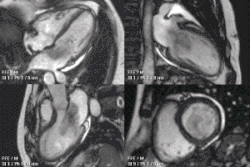

Enlarged right ventricle with poor function in a patient with repaired tetralogy of Fallot by CMR